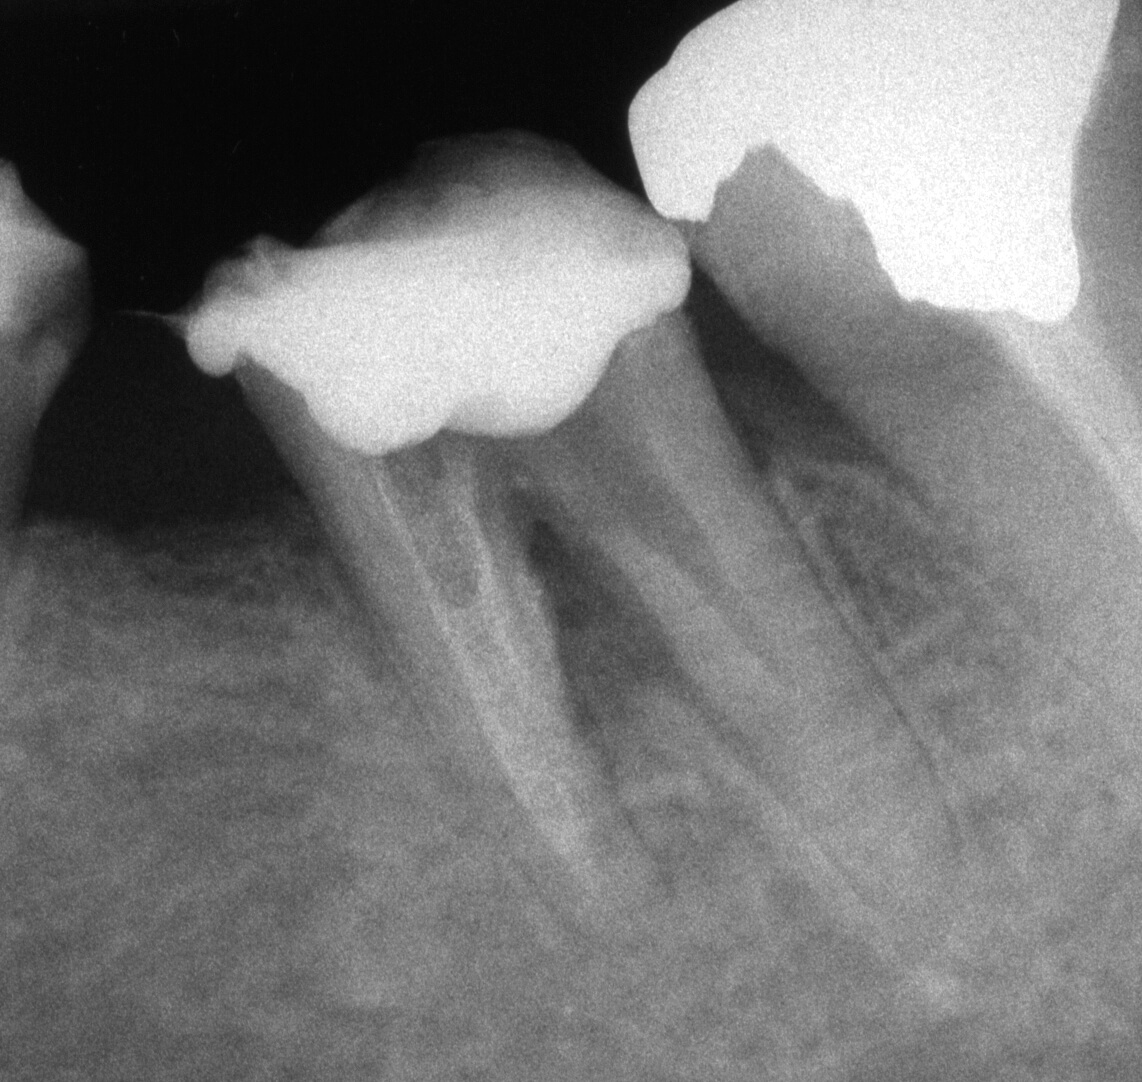

手術用顕微鏡を用いることにより、肉眼のみでは見ることのできないところを明確に観察しながら処置を行うことができます。 このことにより診断や処置の精度をより向上させることができます。歯の根の治療では通常の治療を行っても症状が改善されない場合に、 小さな根の先端部を外科的に切断除去したのち封鎖する手術(歯根端切除手術)を行うことがありますが、そのような精密な手術にも手術用顕微鏡はとても有効です。当センターでは平成19年4月より、 先進医療として、この歯根端切除手術を、診断精度の高いコーンビームCT(歯とその周囲のCT)と併用し行っていましたが、平成28年4月より保険導入されました。